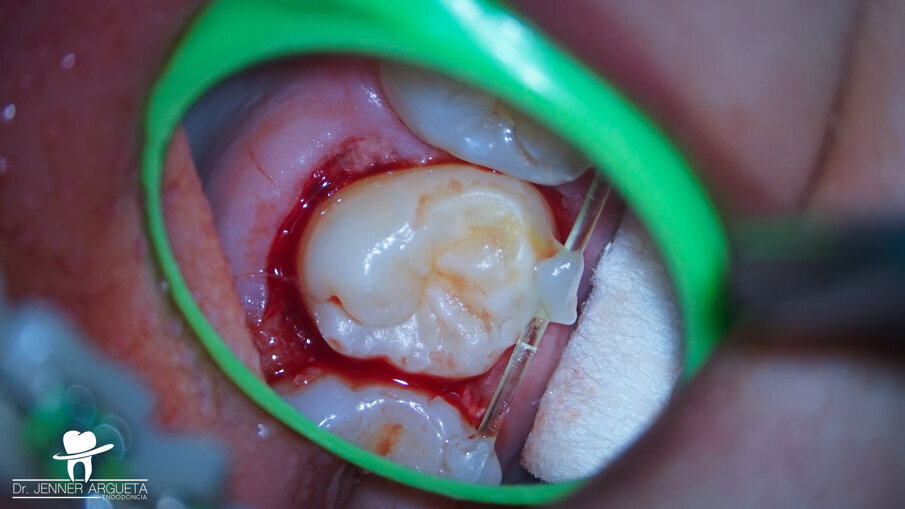

The patient showed up to the clinic eight months later with signs and symptoms of pulp necrosis and acute periapical abscess; a periapical radiolucency was present, and the retromolar area was healed (Fig. 6). In cases like this, where the coronal structure remains intact, it is advisable to take a conservative approach to the root canal therapy, using new technology available in endodontics to achieve good results. The endodontic access opening was created using high-speed burs and ultrasonic tips. The cleaning and shaping protocol was performed with flexible needles and controlled memory files (Aurum Blue, Meta Biomed), especially important properties for entry to the root canals through the conservative access (Figs. 7a & b).

Figs. 7a & b: Clinical photographs of the tooth just before initiating the root canal therapy (a) and just after nishing the endodontic access opening (b).